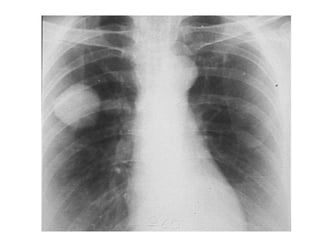

Exposure : You must barely see the thoracic vertebrae

behind the heart

Adequate

Adequate tissue

penetration

Adequate anatomical exposure